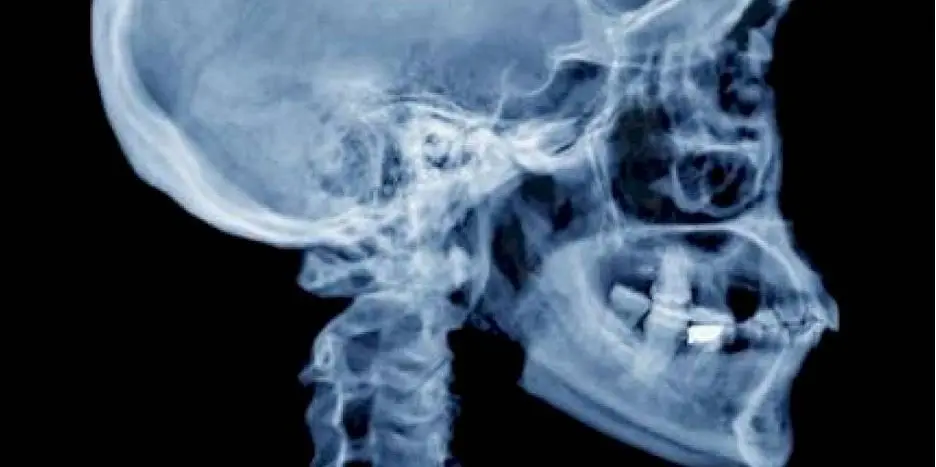

Cráneo

Imagen de un cráneo humano